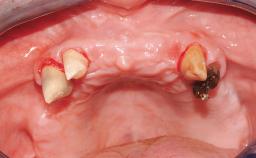

A healthy 31-year-old female patient presented with a failing maxillary left lateral incisor crown. The crown regularly loosened, and the remaining tooth was neither restorable nor rational to treat. The patient had a high smile line, a medium soft tissue biotype with a compromised mesial papilla (shorter than the contralateral one), and a horizontal scar in the buccal soft tissue as a result of past periapical surgery.